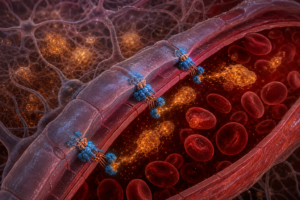

さらに厄介なのは、生物の体内に蓄積される性質を持つことだ。魚が汚染された水で育ち、その魚を人間が食べることで、食物連鎖を通じて私たちの体に取り込まれる。北極圏のホッキョクグマの血液からもPFASが検出されるほど、地球全体に広がっている。

特に懸念されているのが、妊娠中の母親から胎児への移行である。へその緒を通じて栄養と一緒に化学物質も届いてしまう。発達途中の赤ちゃんの脳や臓器は、大人よりもずっと化学物質の影響を受けやすい。